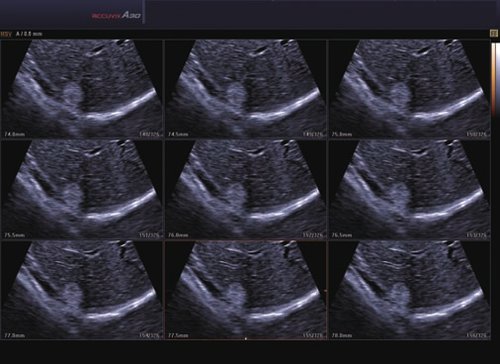

Das Samsung Accuvix A30 ist ein hochwertiges Ultraschallsystem, das mit seiner 3D-Technologie herausragende Ergebnisse ermöglicht. Das Sonographiegerät besitzt 5 Sondenanschlüsse und ist mit 20 unterschiedlichen Schallköpfen kompatibel. Mit dem A30 können Schallköpfe vom Typ Konvex, Mikrokonvex, 3D-Konvex, CW, Phased Array, Linear und Endokavitär verwendet werden. Bei zwei der Sonden handelt es sich um S-VUE Ultraschallsonden, die durch ihre höhere Bandbreite noch feinere Scans erzeugen.

Das Ultraschallsystem hebt sich besonders durch seine 3D-Technologie wie die Face Auto Detection für detaillierte Ultraschallbilder von Föten oder das Volume Shade Imaging, das sich auf die lebensnahe Darstellung von Schattierungen und Hauttönen fokussiert, ab. Mit weiteren wertvollen Technologien wie dem ElastoScan™ werden Tumore schneller erfasst und durch die HD Volumen Bildgebung sowie das DMR+™ eine erstklassige Bildqualität erzielt.

• 3D-Bildmodus

• 4D-Bildmodus.

• FAD™, die Face Auto Detection, stellt das Gesicht eines Fötus besonders detailliert dar. Überflüssige Daten werden entfernt und ein besonders realistisches Bild gezeichnet.

• Volume Shade Imaging, kurz VSI™, visualisiert ein 3D-Bild, das Hauttöne und Schattierungen auf ein qualitativ neues Niveau hebt.

• Die HD Volumen Bildgebung reduziert unerwünschte Streumuster und sorgt für eine präzisere Darstellung der Bilder.